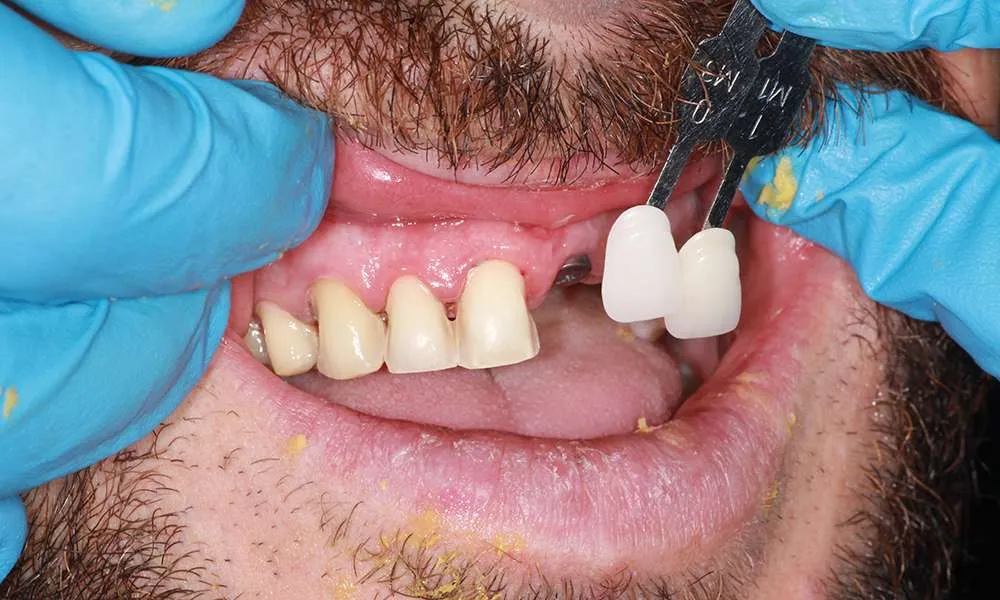

While ultra-thin veneers are a fantastic option for many patients looking to enhance their smile, they may not be suitable for everyone. Ideal candidates are those with healthy teeth and gums who are looking to correct cosmetic issues like discoloration, misalignment/crooked or small gaps. During your consultation, Dr. O'Malley will assess your dental health and determine if ultra-thin veneers are the right choice for you.

The process of getting ultra-thin veneers typically involves several steps. First, during the initial consultation, we will discuss your goals and take impressions and photographs of your teeth. Next, we will minimally prepare your teeth generally less than 0.5mm of preparation (sometimes little or no preparation is needed depending on the design). Then you'll leave with a 'trial smile' and temporary veneers in place, after which we'll have a follow-up appointment the next day for final evaluation of your temporary veneers for tweaks and fitting to help guide the lab to your custom smile. Your veneers are finally crafted in a premier dental lab. Finally you'll return to the office where your custom, ultra-thin veneers are bonded to your teeth using biocompatible materials. The entire process usually takes one to four weeks from start to finish depending on the lab and complexity of the case.

Ultra-thin veneers offer a less invasive alternative to traditional veneers and the procedure is completely different (see above). Traditional veneers often require significant removal of tooth enamel, which can weaken the teeth. In contrast, ultra-thin veneers require minimal tooth alteration, preserving more of your natural tooth structure. This results in a stronger, healthier tooth foundation and a natural-looking appearance. Additionally, ultra-thin veneers are often quicker to apply and cause less discomfort during the procedure.